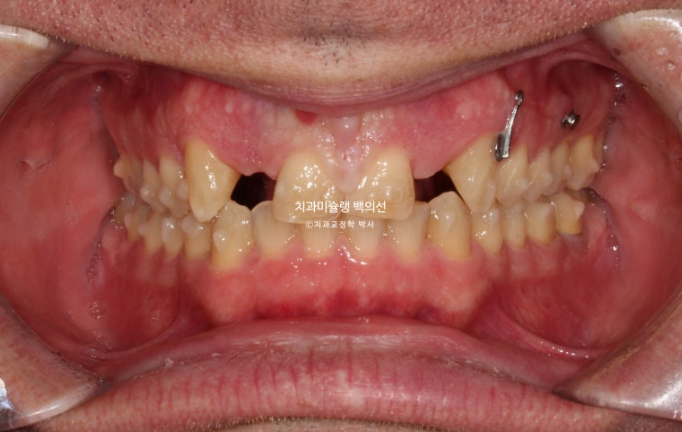

24년 4월까지 5개월간 24개 추가장치를 모두 낀 후 모습입니다.

24.04

중심선은 잘 맞으며 쓰러진 앞니 뿌리 및 중절치 단차는 개선되었습니다.

어금니 교합도 양측 모두 1급 달성되었고 뜨는 부분도 없습니다.

임플란트 식립 부위를 좀 더 안정적으로 만들기 위해서 두번째 추가장치 제작에 들어갑니다.